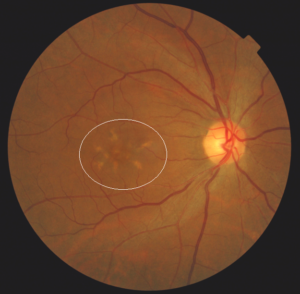

Also at the 2019 visit, the patient’s best-corrected visual acuity was 20/25- in the right eye and 20/25+ in the left eye with near visual acuity of 20/20 (both eyes). All entrance tests and anterior segment slit lamp examination findings were stable, unremarkable and age-appropriate in both eyes. Specific tests performed included extraocular muscle motilities, confrontation visual fields, pupil testing, manifest refraction and dilated fundoscopic examination with 20D and 66D lenses. Amsler grid testing with best near correction was full in each eye. Posterior segment examination with dilation showed mild arterial/venous (A/V) crossing changes with attenuated vessels and an A/V ratio of 1:2 OU. The peripheral retina was unremarkable. Macular findings were stable and significant for the presence of BSPD in both eyes overlying a two-disc-diameter area. The appearance of the butterfly-shaped patterns in 2019 was stable when compared with the 2007 and 2017 retinal photographs (Figures 1-4). The quality of the 2019 photographs was degraded by media blur from the cataracts. Only the 2007 and 2017 retinal images are included in the case report.

![]() Figure 1. 2007: Mydriatic fundus photography of the posterior pole of the right eye, including optic nerve, macula and major retinal vessels. The area of butterfly-shaped pattern dystrophy is circled. |